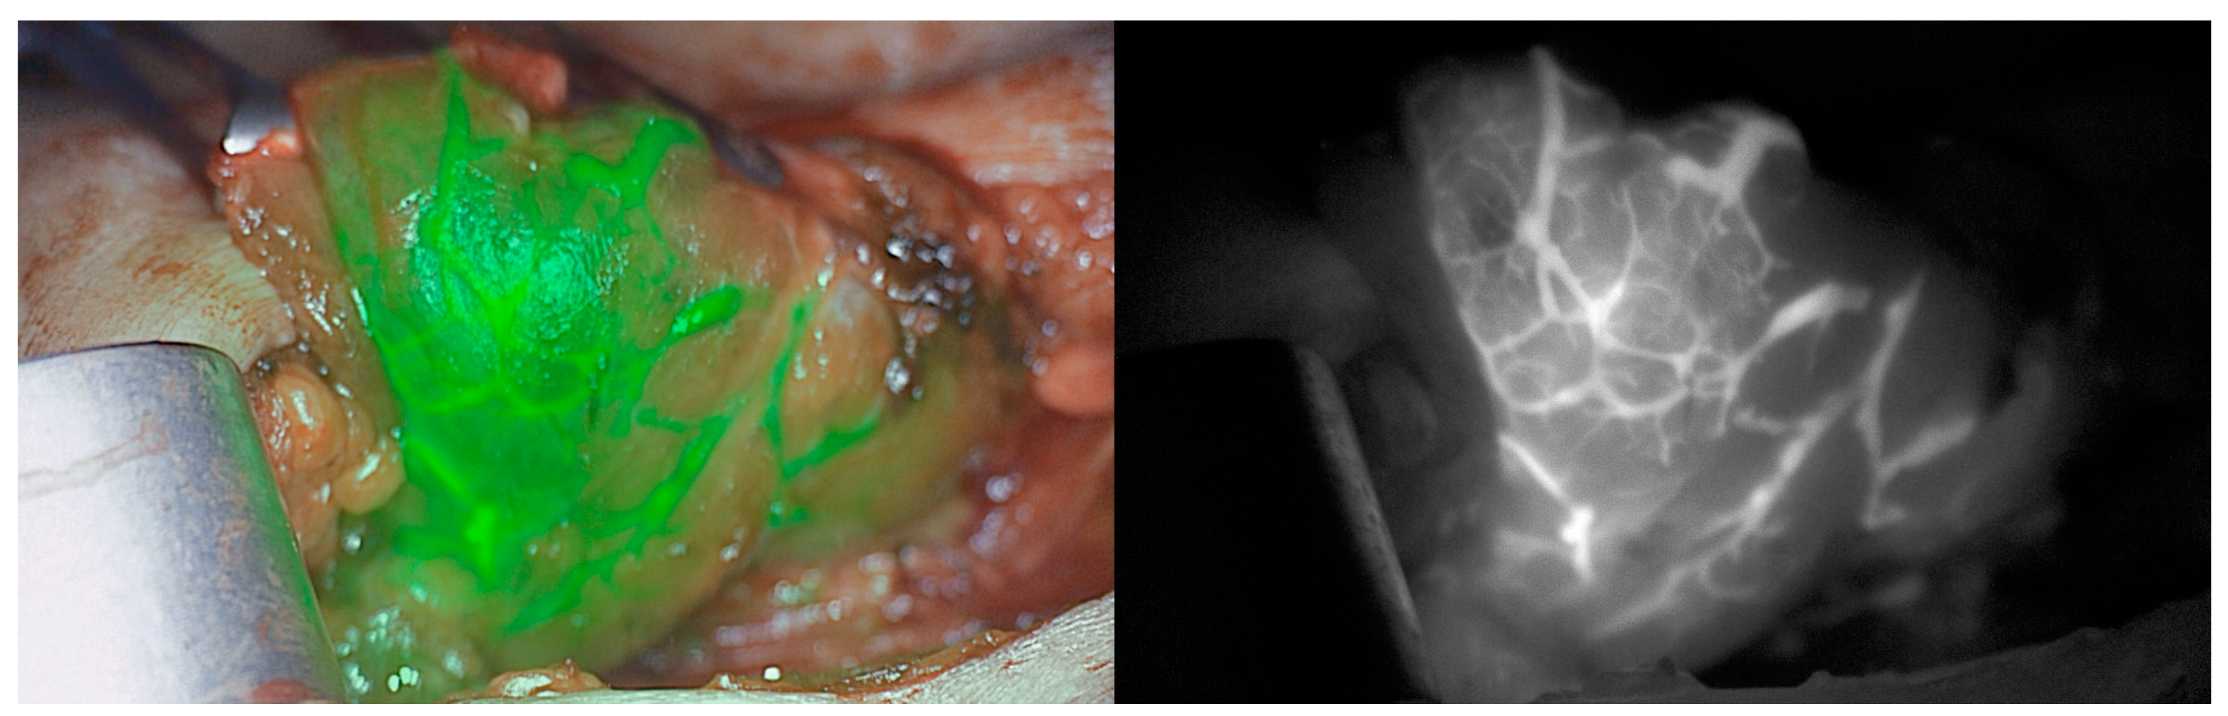

11. Indocyanine Green

12. Indocyanine Green Fluorescence Vs Parathyroid Autofluorescence